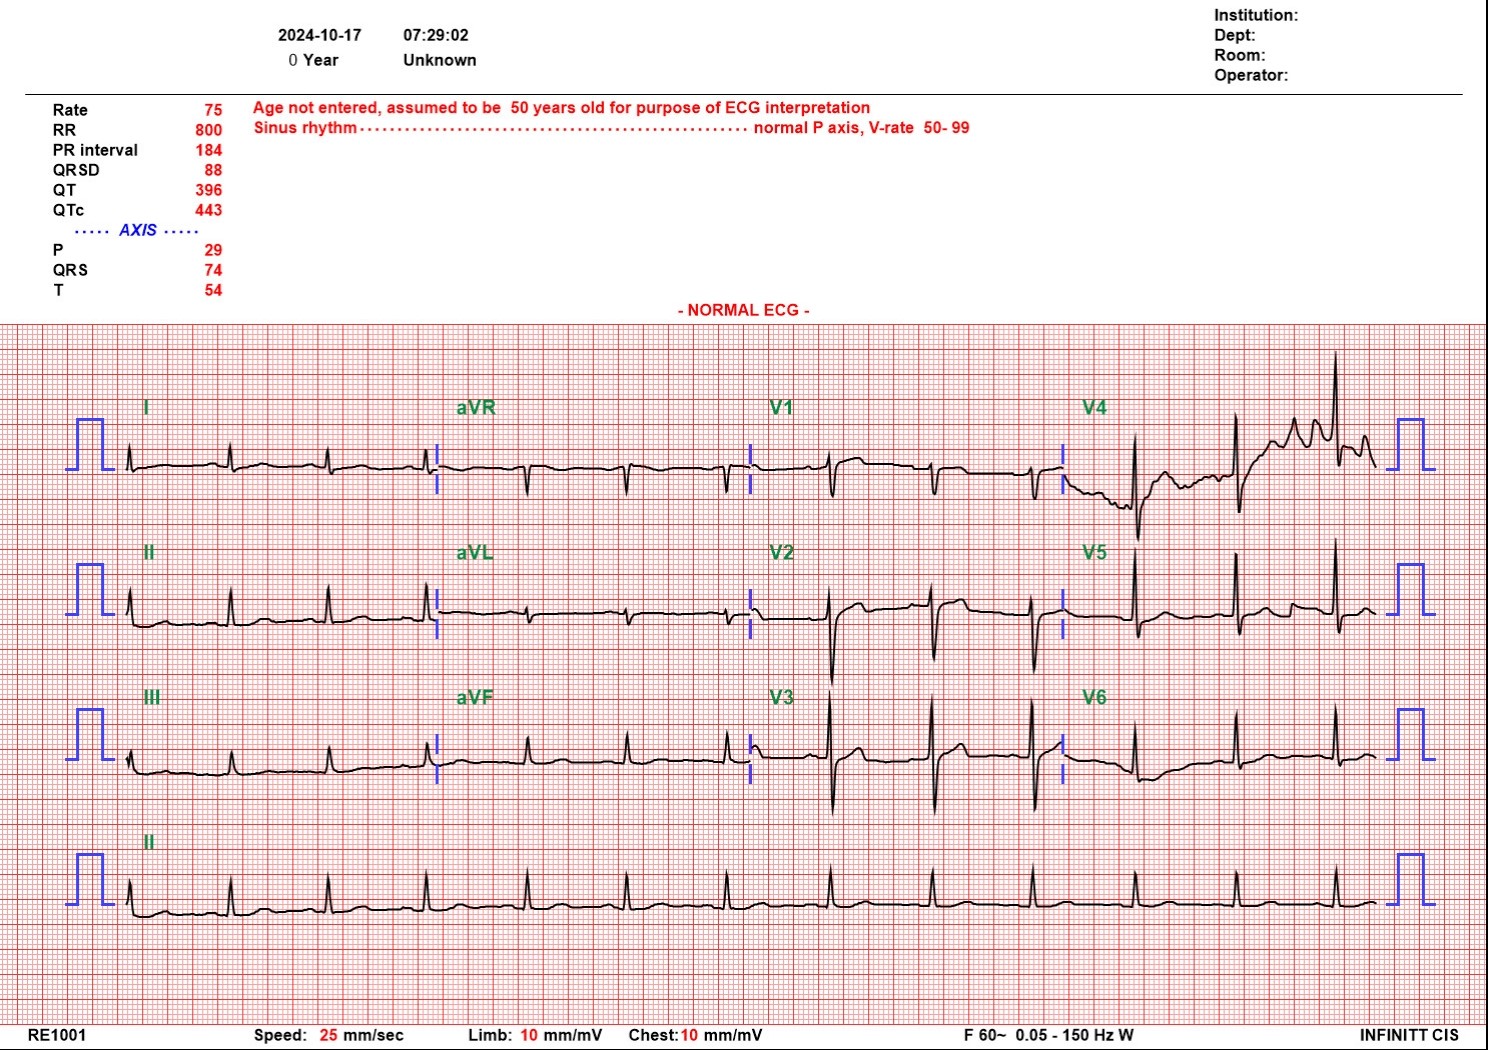

41-year-old male without underlying diseases except smoking presented with intermittent chest pain. Initial vital sign was stable. Physical examination showed no audible murmur and warm extremities. EKG showed no specific ST segment change. Cardiac enzyme was mildly elevation. NSTEMI was diagnosed with GRACE score 51 points.

EKG showed no specific ST segment change. Cardiac enzyme was mildly elevation. Chest X ray showed no cardiomegaly or pulmonary edema.